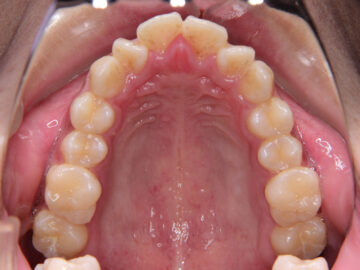

治療後

医師のご提案

開咬(咬み合わせ合わせが開いている状態)は、一番治しにくい不正咬合です。まず、不安定な顎の位置を改善するためにスプリント療法を行った方がいいと考えました。開咬量も大きいので、当院で行っているアンカースクリューではなく、プレートタイプのアンカーを口腔外科でつけてもらって治療することを勧めました。口腔周囲筋機能訓練も重要です。